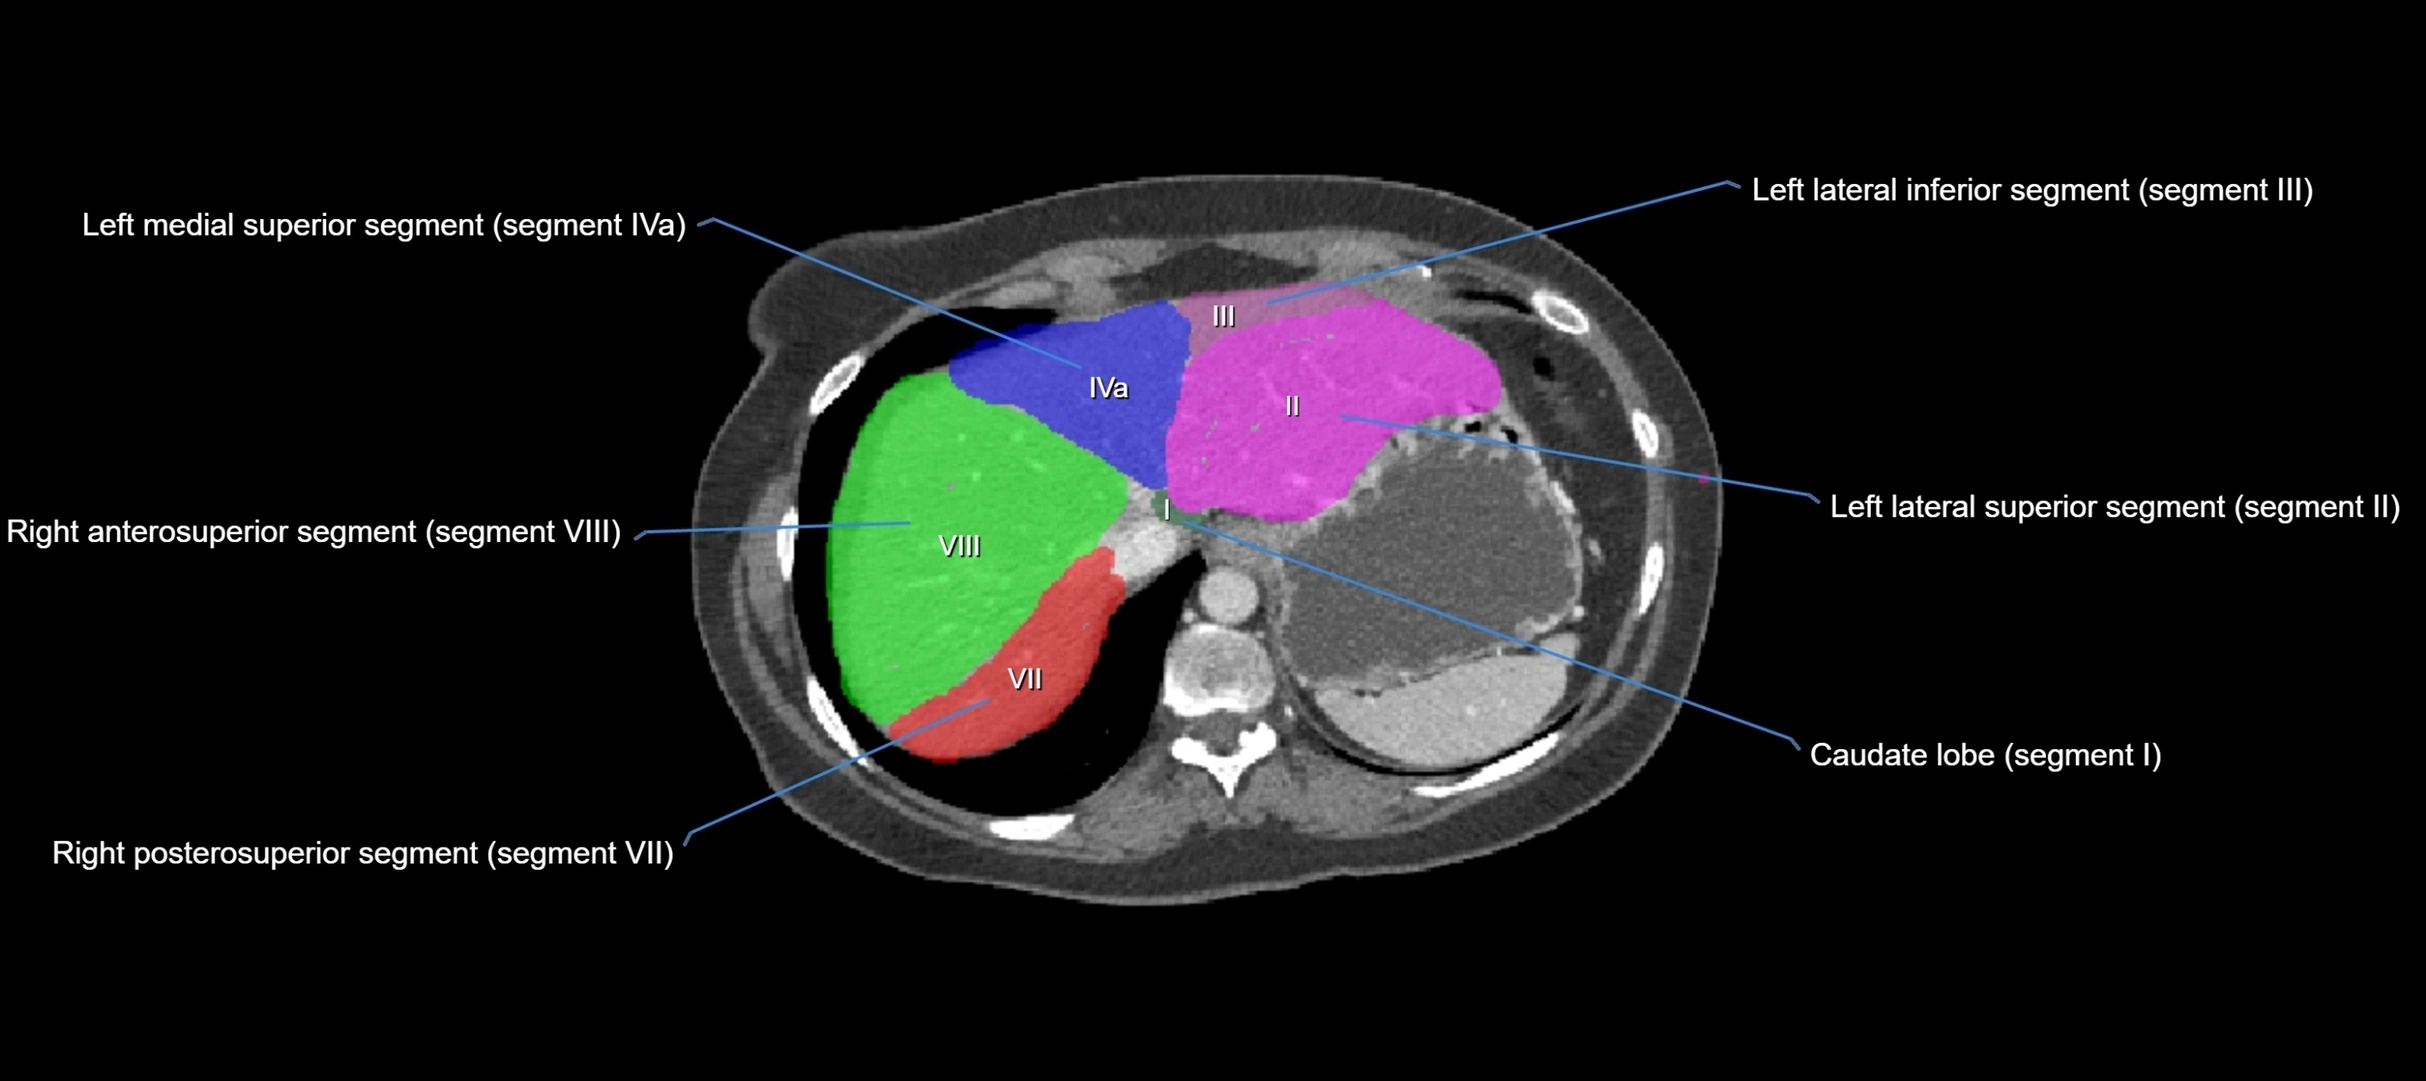

Caudate lobe of liver

The caudate lobe of the liver is a distinct anatomical subdivision of the liver, designated as segment I in Couinaud’s classification. It lies on the posterior surface of the liver, between the fissure for the ligamentum venosum (left boundary) and the groove for the inferior vena cava (IVC) (right boundary). Superiorly, it is related to the posterior liver surface, and inferiorly it is separated from the left lobe by the porta hepatis.

The caudate lobe is unique because it receives dual portal venous and arterial inflow from both the right and left portal veins and hepatic arteries. It also has independent venous drainage directly into the IVC via multiple small hepatic veins, unlike other lobes that drain through the three main hepatic veins.

This anatomical autonomy makes the caudate lobe especially significant in liver surgery, transplantation, and hepatic venous outflow obstruction syndromes (e.g., Budd–Chiari syndrome). Enlargement of the caudate lobe is a characteristic imaging feature in chronic liver disease and cirrhosis.

CT Appearance

CT Pre-Contrast:

• Caudate lobe appears as a soft-tissue density, isodense to the rest of the liver

• Enlargement may be appreciated in cirrhosis or Budd–Chiari syndrome

CT Post-Contrast:

• Homogeneous enhancement in the portal venous phase, similar to rest of liver

• Independent venous drainage into the IVC may be visualized

• Lesions follow characteristic CT enhancement patterns (HCC: arterial hyperenhancement with washout; hemangiomas: peripheral nodular enhancement with centripetal fill-in)

CT Venous Phase (functional significance):

• Caudate lobe often enhances relatively more than other lobes in Budd–Chiari syndrome, due to preserved venous outflow

CT Image

image